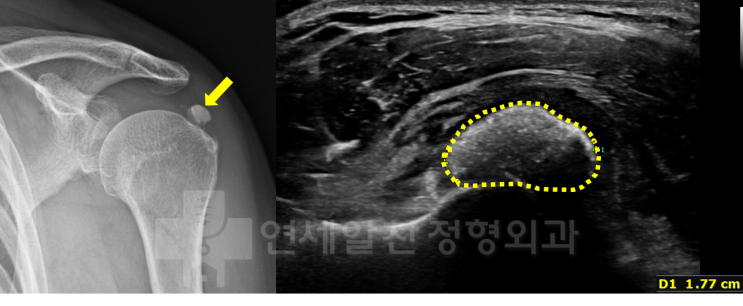

거대한 석회성 건염에서 관절경을 통한 석회 제거술 및 극상근 봉합술(side to side)

43에 여자 환자로 우측 어깨의 극심한 통증을 주소로 내원하였다. 환자는 내원 일주일 전부터 극심한 통증...